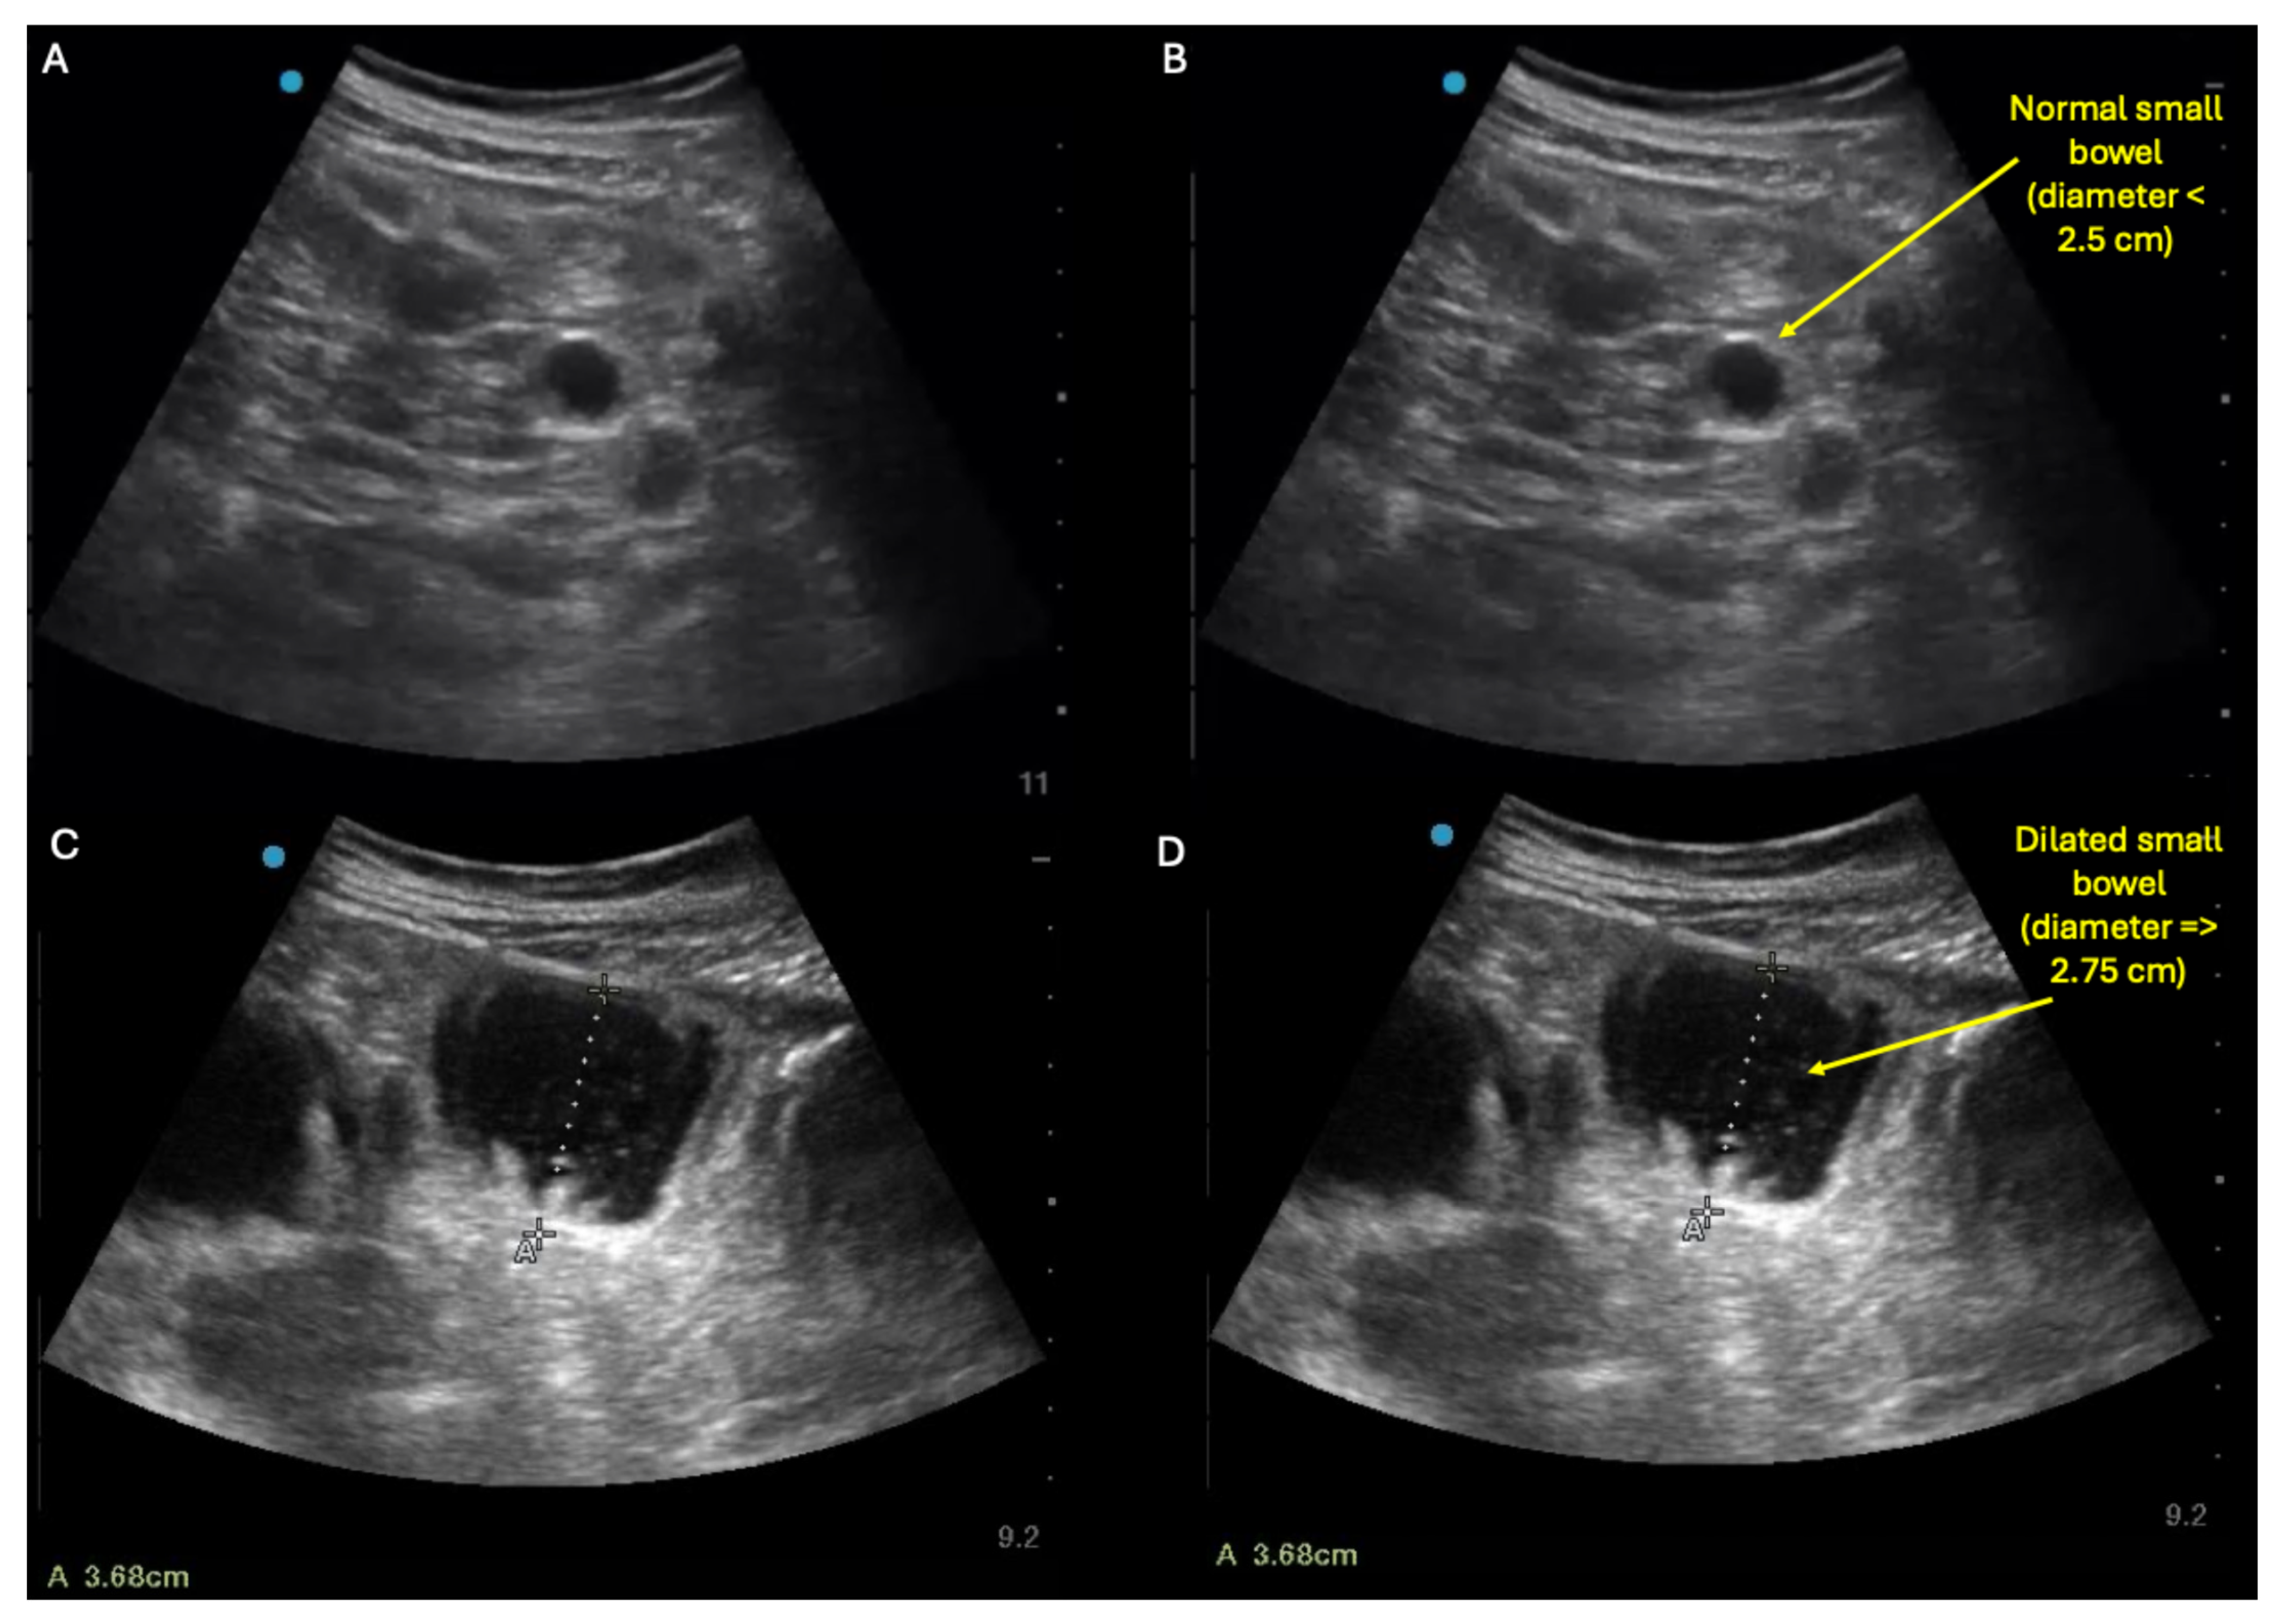

- Abramson, L.; Olive, J.K.; Lefler, B.; Wu, L.; Bowman, A.; Simpson, T.; Vatsaas, C.; Yanamadala, M.; Bronshteyn, Y.S. Point-of-care Ultrasound to Screen for Gastrointestinal Dysfunction: Image Acquisition and Interpretation. J. Vis. Exp. 2025, e68603. [Google Scholar] [CrossRef] [PubMed]

- Shokoohi, H.; Al Jalbout, N.; Peksa, G.D.; Mayes, K.D.; Becker, B.A.; Boniface, K.S.; Lahham, S.; Secko, M.; Chavoshzadeh, M.; Jang, T.; et al. Optimal bowel diameter thresholds for diagnosing small bowel obstruction and surgical intervention with point-of-care ultrasound. Am. J. Emerg. Med. 2024, 84, 1–6. [Google Scholar] [CrossRef]